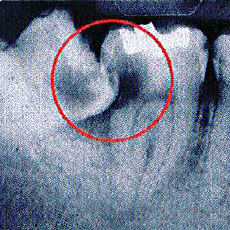

4. 骨の中の膿ふくろ(膿痬、のう胞)

歯の根の先に膿のふくろが出来ていることがよくあります。これを歯根のう胞といいます。

あごの骨の中で、気づかないうちに徐々に大きくなることがあります。歯の根の治療で治ることもありますが、手術で取り除かなくてはならないこともあります。これは、お口全体のレントゲンを撮影することで、発見できます。当院の定期検診では、レントゲンを撮影した際に必ず確認しています。

のう胞